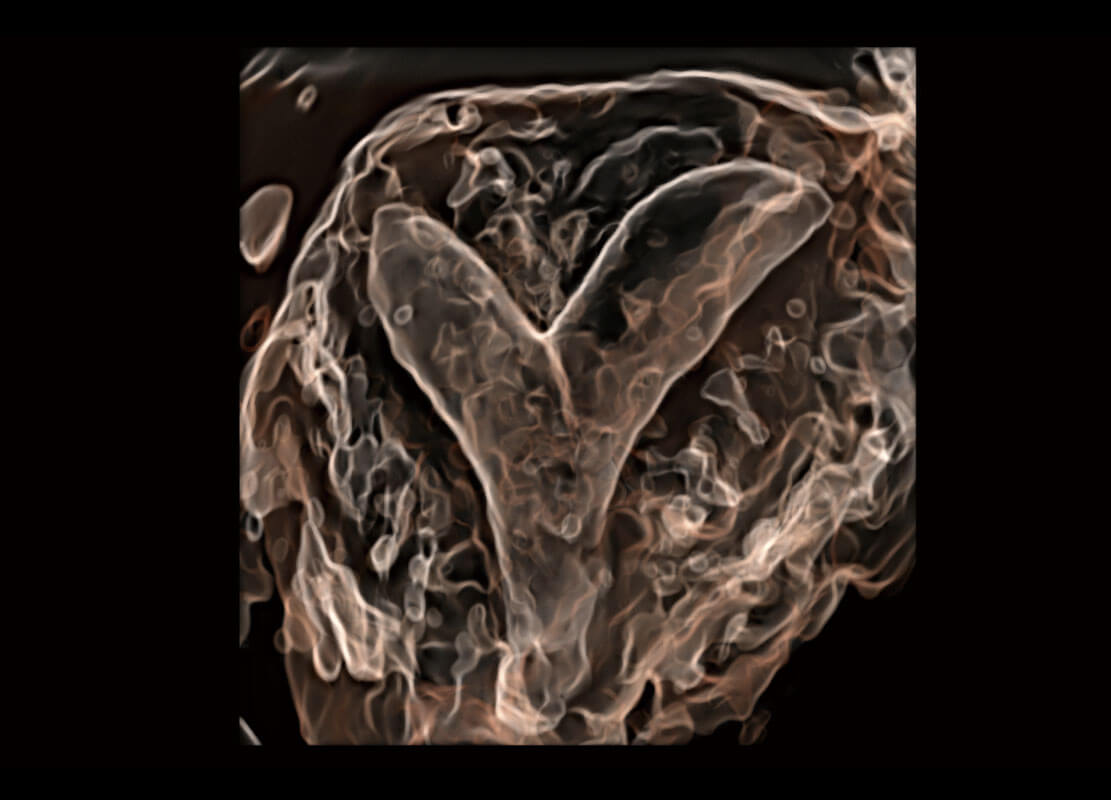

• 腔内三维-宫内节育器

• 腔内三维-光影成像